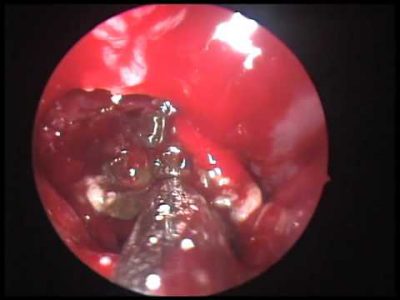

• эндоскопия позволяет выявить присутствие гноя в среднем проходе носовой полости,